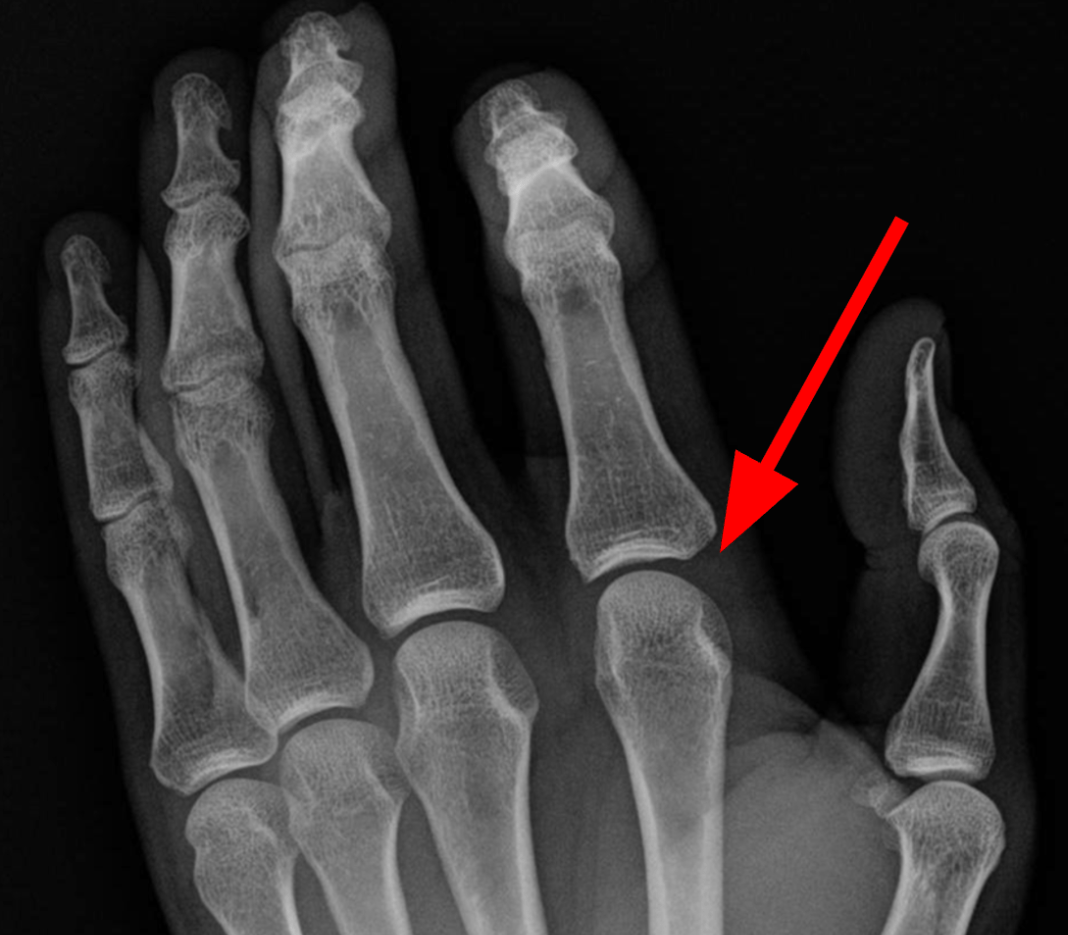

Describe the specific anatomical location of this fracture.

Distal end of the left femur.